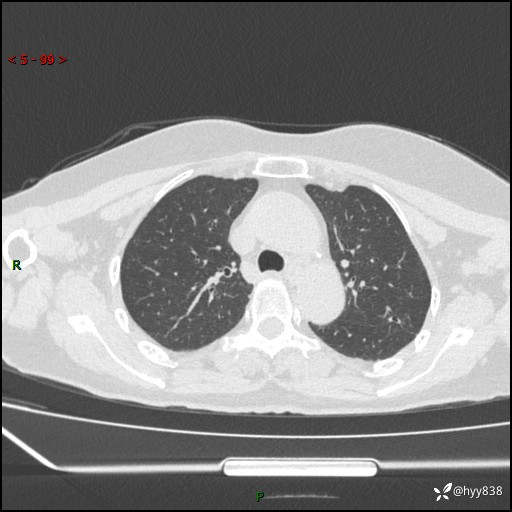

老年女性,偶然发现肺结节10天。结节不大,空洞不小,还牵拉胸膜---结果公布~

现病史:患者10余天前因“左侧鼻塞伴鼻腔异味2月”就诊于我院耳鼻喉科,查胸部CT示:左上肺结节影,建议复查。患者偶有咳嗽、咳痰,多咳白痰,无畏寒、发热,无胸痛、呼吸困难等,现为进一步明确肺结节性质,就诊于我科门诊。现以“孤立性肺结节”收住我科。 起病来,患者精神、食欲、睡眠尚可,体力、体重无明显变化。

胸部CT(2024.7.16)